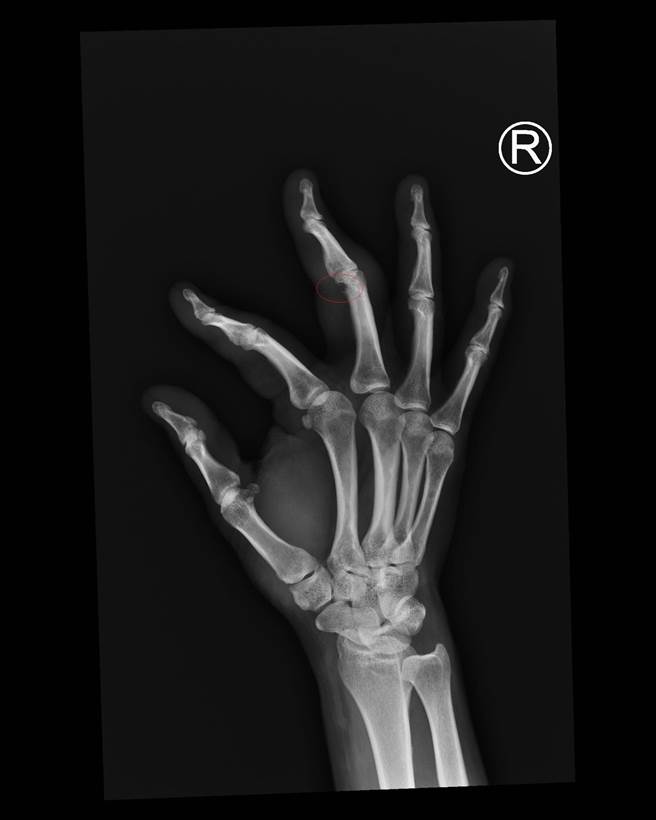

林妇右手X光片,中指关节骨头被侵蚀,缺了一小块。(院方提供/吴建辉彰化传真)

住在秀水乡林妇为家庭主妇,每天早上都会带着爱犬到公园散步慢跑,直到最近发现脚步跟不上小狗,才到医院求诊,被确诊为类风湿性关节炎后,经过X光显示两手的食指及中指关节些微肿胀变形,双脚也是,右手中指关节骨头更有被侵蚀情况,吓得她害怕以后会不会失能无法动弹。